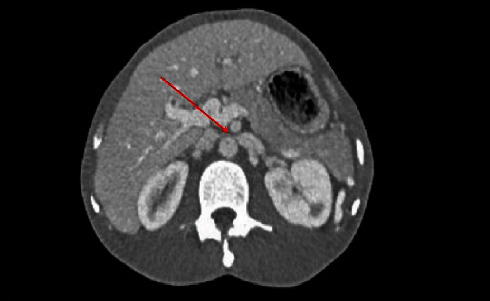

Nutcracker syndrome (NCS), a rare but impactful vascular condition, emerges from the compression of the left renal vein by adjacent major arteries, leading to a diverse array of symptoms such as hematuria, flank pain, and renal challenges. Highlighting the case of a 30-year-old male with an atypical presentation of NCS, this report explores the diagnostic complexities arising from its varied presentations and therapeutic options. It emphasizes the critical role of computed tomography (CT) in unveiling the underlying vascular constriction. Through this lens, the case underscores the necessity of considering NCS in the differential diagnosis of abdominal pain, advocating for a prompt and accurate diagnosis to guide effective management strategies, ranging from conservative approaches to surgical intervention. This stresses the importance of heightened awareness and ongoing research for optimizing patient outcomes in the face of this elusive condition.